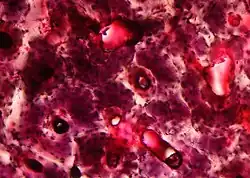

In der Histologie werden Gewebeproben untersucht. Dazu werden mikrometerdünne, gefärbte Gewebsschnitte hergestellt und am Lichtmikroskop beurteilt. Die elektronenmikroskopische Untersuchung von wesentlich dünneren Schnitten (0,01–0,5 µm) fällt vorwiegend in den Forschungsbereich.

Die feingeweblichen Untersuchungen in der Medizin dienen verschiedenen Zwecken wie der Frühdiagnose von Tumoren (z. B. Magenbiopsie), Klassifizierung von Tumoren (gutartig/bösartig), Nachweis von Stoffwechselerkrankungen und parasitären, bakteriellen, entzündlichen Erkrankungen und der Hilfe zur Therapiewahl. Man spricht von morphologischer Diagnostik, da der Befund anhand des Erscheinungsbildes und des färberischen Verhaltens der Gewebestrukturen erstellt wird.

Die Verarbeitung von Formaldehyd-fixiertem, Paraffin-eingebettetem Gewebe inklusive der Hämatoxylin-Eosin-Färbung stellt die weltweite Routine-Methode der Pathologie dar und dauert durchschnittlich ein bis zwei Tage von der Probenannahme bis zur Befundung. Im Gegensatz zum klinisch-chemischen Labor sind viele Arbeitsschritte von Hand durchzuführen. Besonders die Schnittherstellung am Mikrotom bedarf großen Geschicks.

Es gibt eine Unzahl verschiedener histologischer Färbungen, die im Laufe der letzten 120 Jahre entwickelt wurden. Der Großteil stammt aus den ersten 30 Jahren des vorigen Jahrhunderts. Im modernen Histolabor hat sich eine überschaubare Anzahl an Färbungen durchgesetzt. An erster Stelle steht die Hämatoxylin-Eosin-Färbung (HE-Färbung) als Routine- und Übersichtsfärbung. Dafür werden meist computergesteuerte Färbeautomaten eingesetzt. Daneben werden für bestimmte Fragestellungen sogenannte Spezialfärbungen (meist von Hand) durchgeführt.